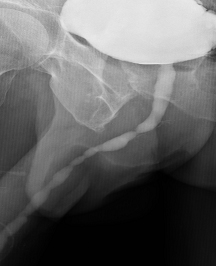

Tumores Primarios De La Uretra En El Varon Sciencedirect - Uretrografia que muestra una estenosis uretral en el hombre (etiquetada como verengung que se traduce como.